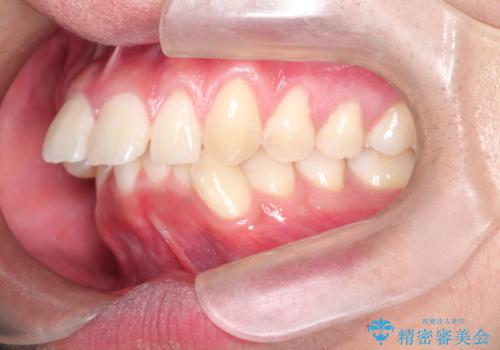

インビザラインによる出っ歯の矯正

- 出っ歯と下の歯のガタガタを主訴に来院されました。

上の奥歯を後方に移動させて、スペースを作り前歯を内側に引っ込める計画としました。

インビザラインをしっかり使用していただいたので、スムーズに治療をおえることができました。